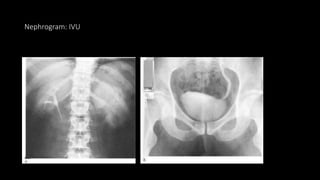

Nephrogram: IVU

Intravenous urography (IVU)

• Traditionally the first-line imaging modality. Not ideal if there is poor renal

Findings

• Direct visualization of a ureteric calculus.

• A delayed nephrogram and filling of the collecting system with a standing column

of contrast in the ureter to the level of the calculus which persists post

micturition.

• The length of delay in the appearance of contrast in the collecting system gives an

idea of the degree of obstruction.

• Affected kidney is modestly enlarged.